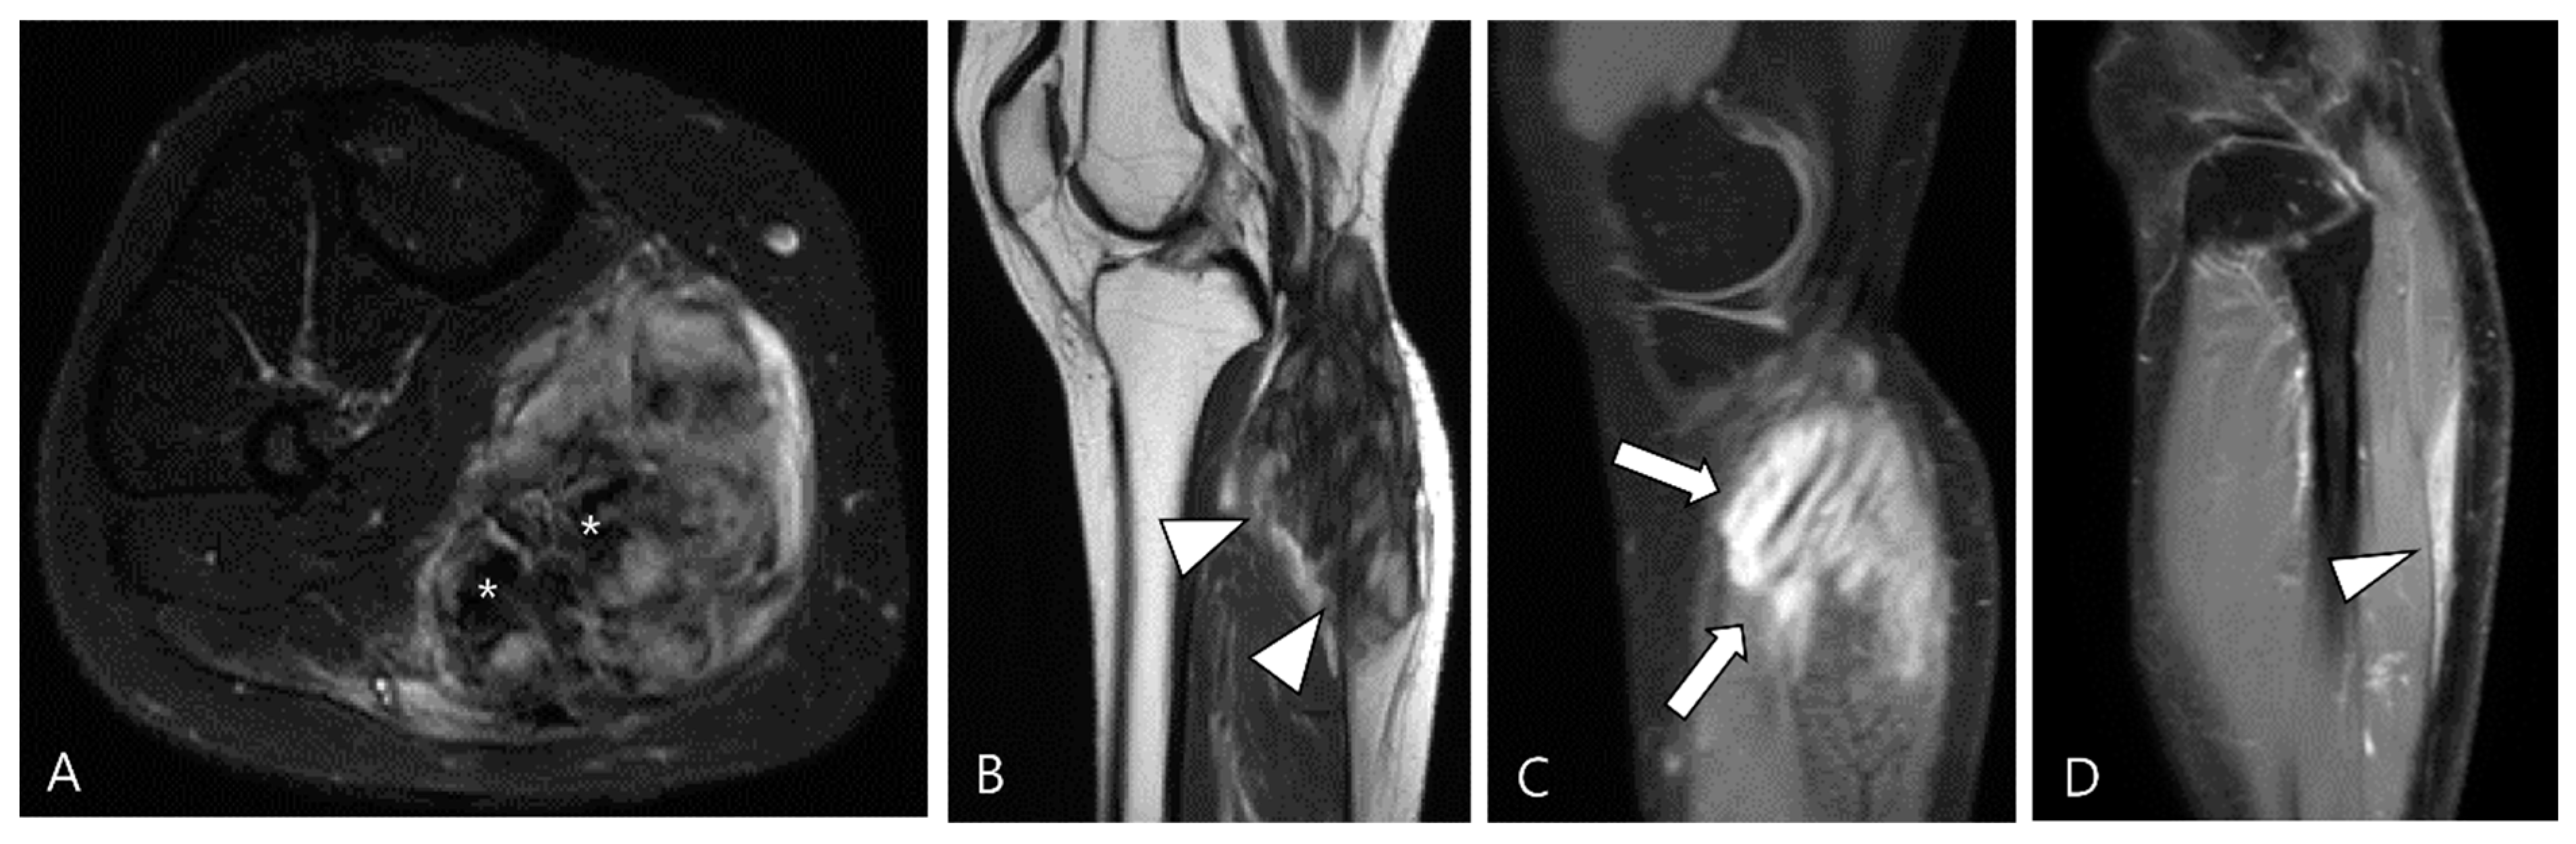

2.4. Relationship to Adjacent Structures of D-TSGCT

4. MRI Findings for D-TSGCT on Follow-Up MRI

4.2. Checklists on Follow-Up MRI for D-TSGCT